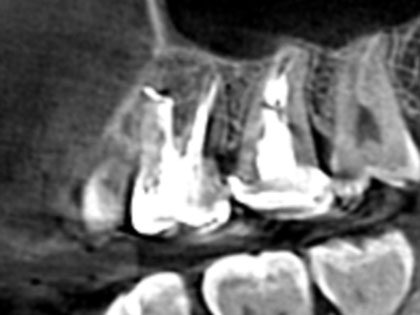

• 歯根端切除の術前1

• 歯根端切除の術前2

• 歯根端切除の術前3

• 歯根端切除の術前4

• 歯根端切除の術前5